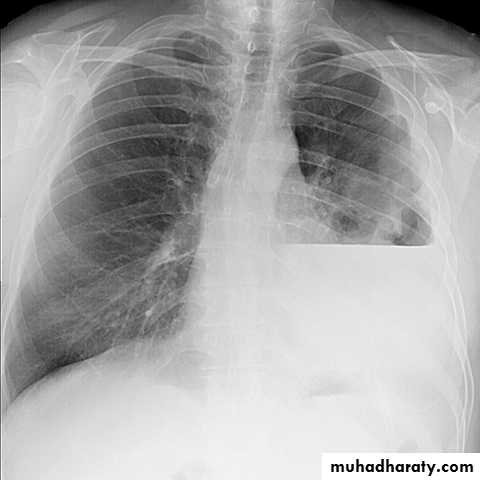

X-ray hemothorax

X-ray pneumohemothorax